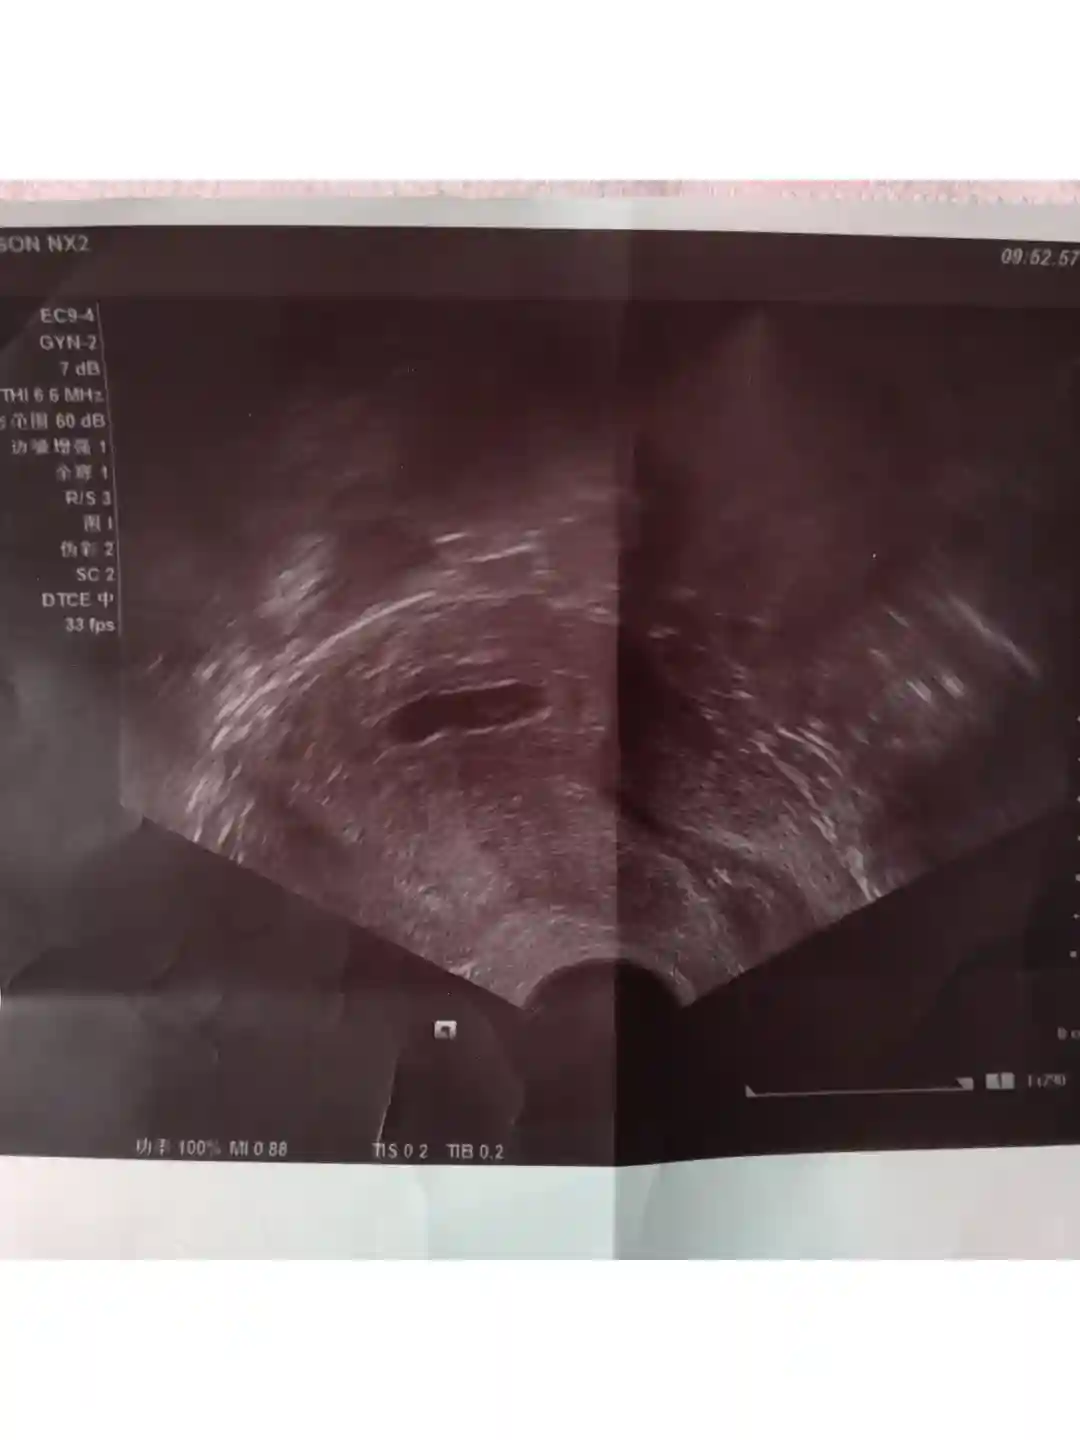

🌷下面和姐妹们分享一下近期身体变化情况,移植后Day17—20腰酸非常严重,可能是因为节后开始上班,比较累的原因,一到中午腰就直不起来,要躺几个小时才能缓过来。

#南京妇幼保健院 #试管早孕期#囊胚移植#孕期b超 #试管日常